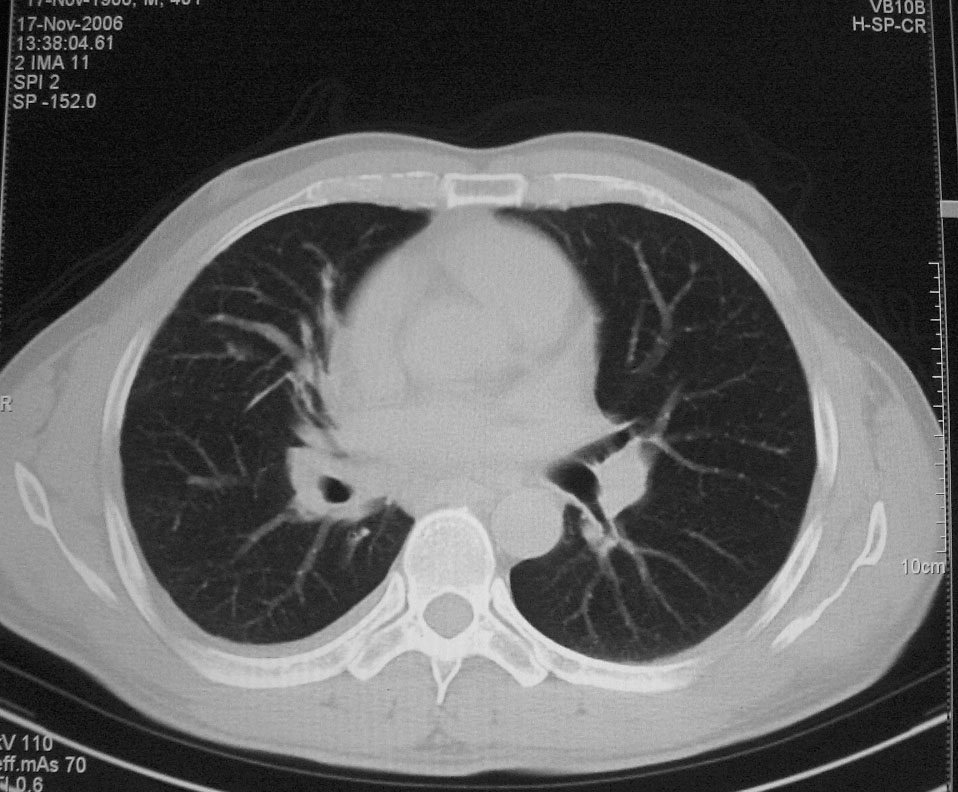

标题: CT5485:[原创]肺部占位请讨论

右上肺ca并肺不张,纵隔淋巴结转移

右肺上叶中央型肺癌并上叶肺不张、纵隔淋巴结肿大

右上叶支气管后壁明显增厚,支持右肺上叶中央型肺癌伴右上叶肺不张、纵隔淋巴结肿大。

右上叶支气管后壁明显增厚,支持右肺上叶中央型肺癌伴右上叶肺不张、纵隔淋巴结肿大。建议支气管镜检查。

右上肺中央性肺癌伴右侧胸腔少量积液!右上肺胸膜下还有一小病灶,不完全排除结核,但个人支持恶性肿瘤!建议早穿刺活检。

右上叶支气管开口变窄,纵隔见肿大的淋巴结。支持右上叶中心型肺癌并右上叶不张纵隔淋巴结肿大。

右肺上叶中央型肺癌并上叶肺不张、纵隔淋巴结肿大.右侧少量胸腔积液。

右肺上叶支气管后壁增厚,呈鼠尾状狭窄,纵隔内未见明显增大的淋巴结影,考虑为中央型肺癌伴右上肺不张